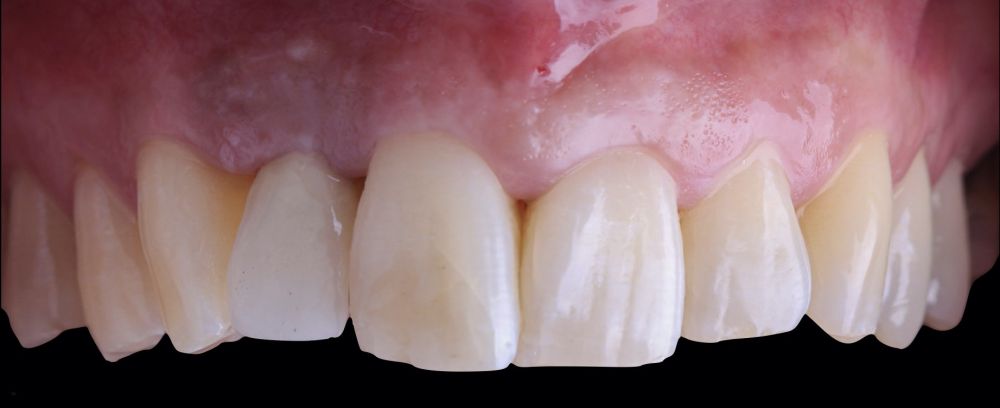

-Fase III: tres meses tras la colocación del implante, la situación del tejido blando era favorable (Figuras 5 y 6). Se tomó una impresión digital mediante escáner intraoral para la realización de un provisional atornillado de polimetilmetacrilato (PMMA). Respecto a la corona implantaria definitiva se realizó una restauración cemento-atornillada con una interfase de titanio nitrurado adaptando el diseño al perfil de emergencia ya consolidado con la prótesis provisional. La corona se realizó por CAD-CAM en zirconio con reducción completa y estratificación de cerámica feldespática de recubrimiento para zirconio (Figura 7).

El resultado clínico final fue satisfactorio cumpliendo las demandas estéticas del paciente. Los tejidos blandos estaban morfológicamente y dimensionalmente estables sin ningún signo de inflamación. Sin embargo, los cambios del tejido blando periimplantario (espesor volumétrico vestibular) fueron demostrados de manera cualitativa y cuantitativa (Figuras 8 y 9). En el postoperatorio inmediato (T1), la ganancia media obtenida al comparar T0 frente a T1 fue de 0,88 ± 0,15 mm con un incremento máximo de 1,1 mm. Al comparar T0–T2, se observó una ganancia media de 0,73 ± 0,23 mm. Es decir, se ha producido una contracción de volumen de 0,16 mm desde la colocación del injerto (T1) hasta pasado un mes y medio (T2).

El caso presentado representa un enfoque multidisciplinar ante la pérdida de un diente en el sector estético. Conviene destacar que el tratamiento minucioso de los tejidos duros y blandos, así como la planificación mediante cirugía guiada aumenta la precisión en relación con la posición ideal desde el punto de vista prostodóncico, lo que repercutirá en la estabilidad a largo plazo de tejidos duros y blandos. El presente análisis volumétrico sugiere que tras la realización de un injerto de tejido conectivo se produce una ganancia que tras un mes y medio disminuye.